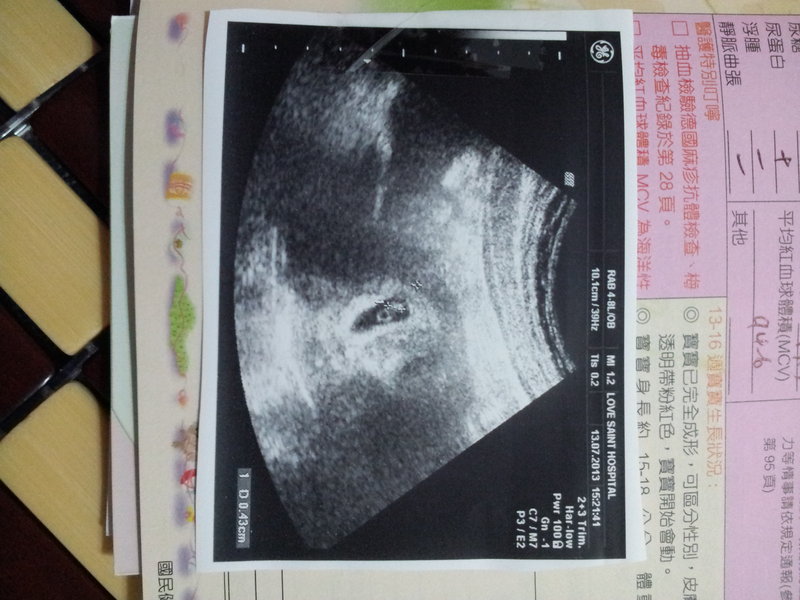

進去以後醫生說檢查一下吧

結果發現胚胎有點不一樣

量了一下0.4CM

接著醫生說

讓我們聽一下"世界上最美妙的聲音"吧

我跟老婆對看了一下

其實眼淚已經再打轉

BABY~~爸爸不要求啥

現在只希望妳跟媽媽都健健康康

我才能安心的工作

預產期2014/03/04

今天拿到媽媽手冊了^^